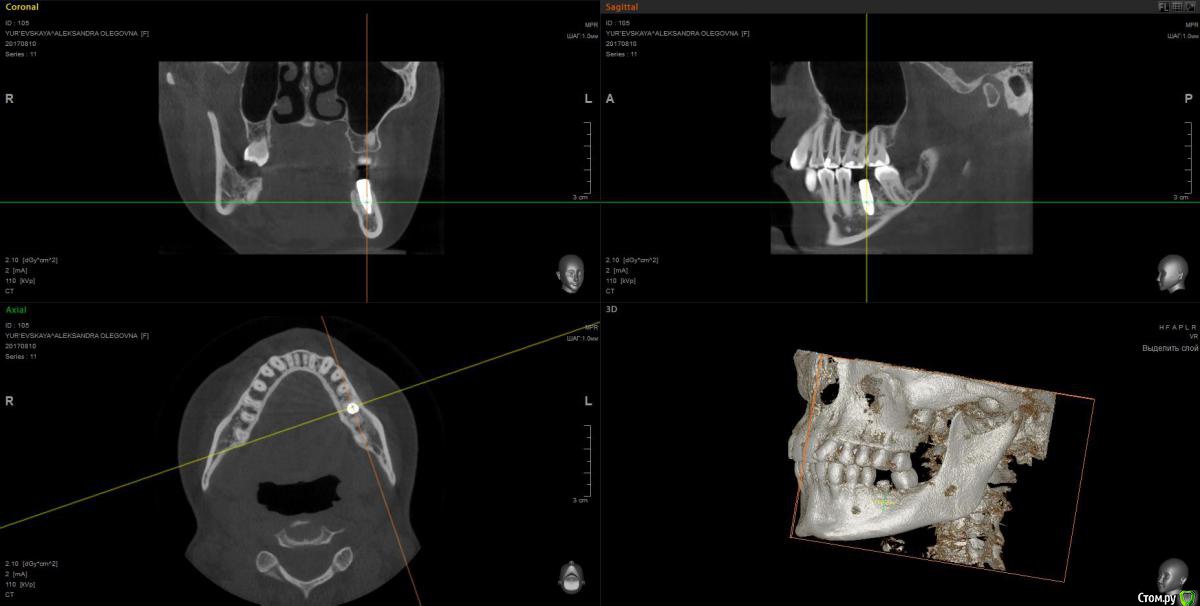

wladdX Опубликовано 28 сентября, 2017 Поделиться Опубликовано 28 сентября, 2017 Ссылка на комментарий

Павел7809 Опубликовано 28 сентября, 2017 Поделиться Опубликовано 28 сентября, 2017 (изменено) А восьмой зуб давно удаляли? Возможно это моя больная фантазия, но покрутив кт я увидел 2 канал нижнечелюстного. Посмотрел еще раз, он там точно есть Изменено 28 сентября, 2017 пользователем Павел7809 Ссылка на комментарий

Kobusha Опубликовано 28 сентября, 2017 Автор Поделиться Опубликовано 28 сентября, 2017 (изменено) А восьмой зуб давно удаляли? Возможно это моя больная фантазия, но покрутив кт я увидел 2 канал нижнечелюстного. Посмотрел еще раз, он там точно естьВосьмерку со стороны имплантата - в мае. Ретинированный зуб был. Нижнечелюстного нерва? а что это значит? =) наличие данного канала? Изменено 28 сентября, 2017 пользователем Kobusha Ссылка на комментарий

Kobusha Опубликовано 28 сентября, 2017 Автор Поделиться Опубликовано 28 сентября, 2017 (изменено) upd. по истории: сходила к имплантологу. Посмотрел кт еще раз(то, которое выше), сделал прицельный снимок. (отдавать или пересылать на почту отказались). ничего не видит. причину боли определить не может, посылает к терапевту. и хочет опять устанавливать временную коронку в ближайшее время(его рабочая версия, что в прошлый раз - коронка люфтила, давая болевой синдром). Но боль-то присутствует.Буду признательна за какие-либо альтернативные точки зрения. Изменено 28 сентября, 2017 пользователем Kobusha Ссылка на комментарий